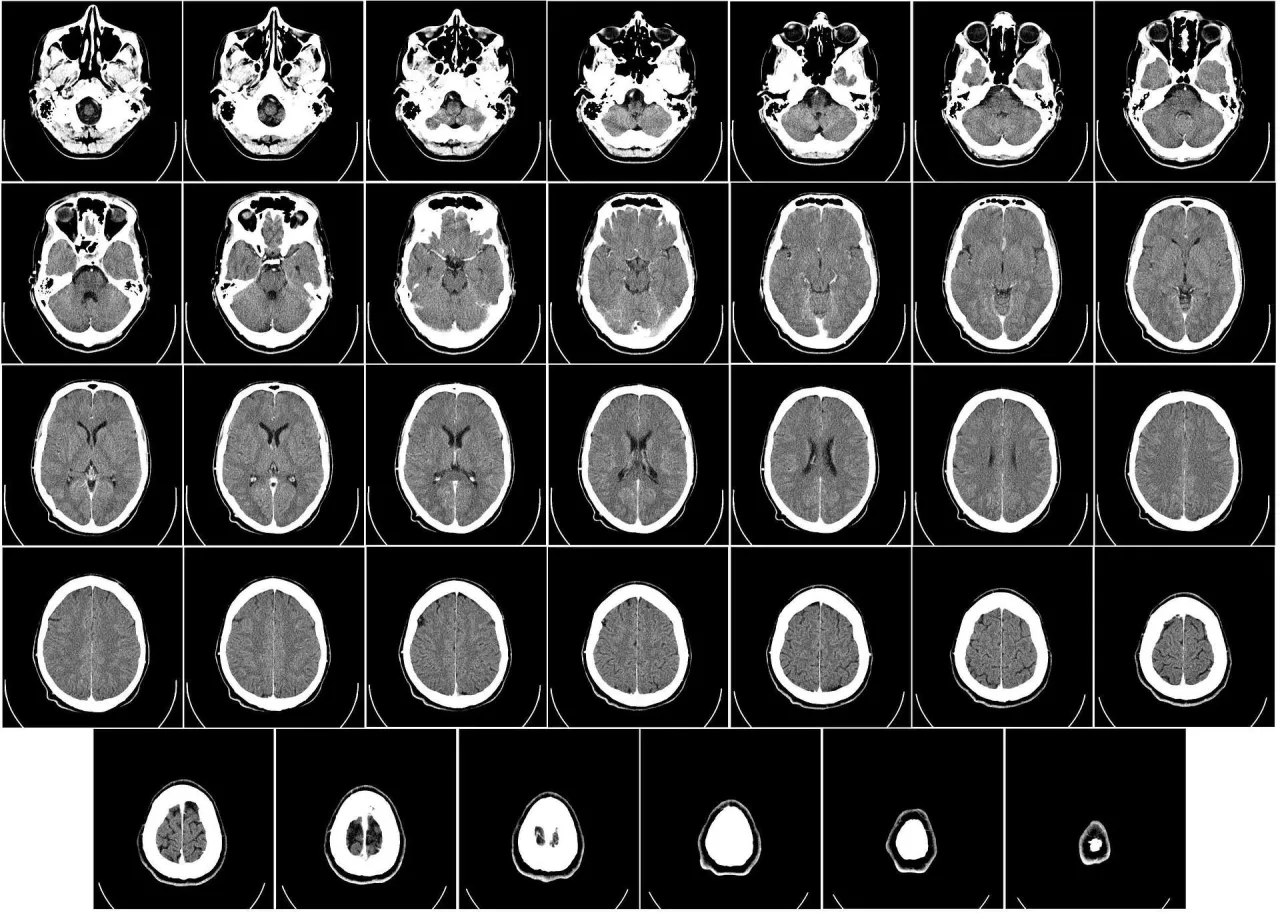

Czas oczekiwania na wyniki tomografii głowy jest istotnym zagadnieniem dla wielu pacjentów, którzy pragną uzyskać informacje o swoim stanie zdrowia. W zależności od placówki, w której wykonano badanie, czas ten może się znacznie różnić. W przypadku badań realizowanych w ramach NFZ, wyniki mogą być dostępne od 1 do 2 tygodni. Natomiast w prywatnych klinikach czas oczekiwania jest zazwyczaj krótszy, a w niektórych przypadkach wyniki mogą być gotowe już po 10 dniach roboczych.

Warto również zauważyć, że w sytuacjach nagłych lub gdy badanie jest wykonywane w ramach hospitalizacji, wyniki mogą być dostępne nawet tego samego dnia. W artykule przyjrzymy się szczegółowo czasom oczekiwania na wyniki tomografii głowy w różnych placówkach oraz czynnikom, które mogą wpływać na te terminy.